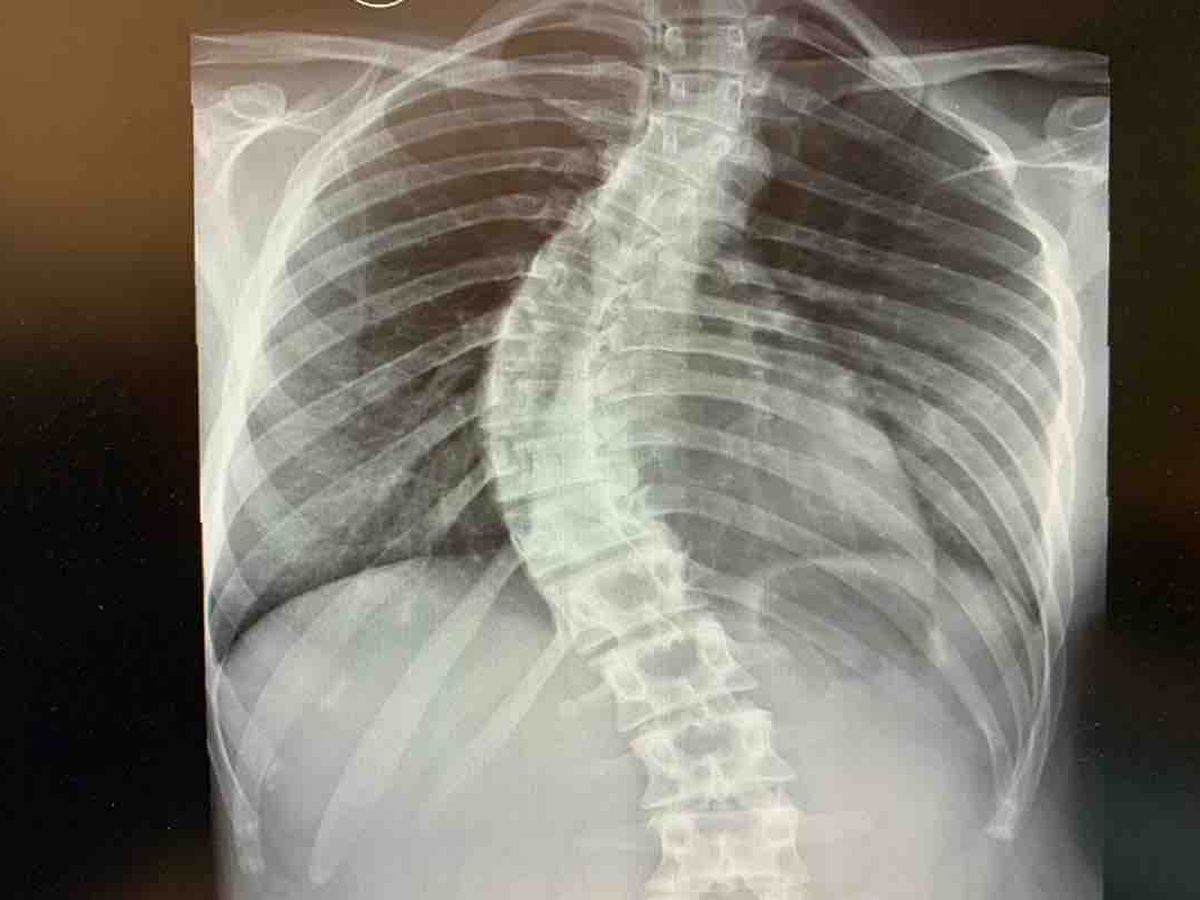

Soy andrea, tengo 23 años y esta es mi columna. A los 14 años empece con dolores de espalda y muchas contracturas lo que me hizo acudir al especialista, el cual vio enseguida que tenia una escoliosis. A base de mucho fisio y ejercicios podía controlar el dolor.

Me dedico al deporte y vivo para ello, soy monitora de actividades dirigidas y me encanta este trabajo y ayudar a la gente a estar en forma. Hace mas o menos un año empezó a dolerme fuertemente la lumbar, evidentemente mi curvatura había ido a más !

El problema no es solo en la curvatura sino que mis costillas al estar rotadas me están oprimiendo los pulmones y por lo tanto disminuye mi capacidad pulmonar..El fin de mi patología es pasar por el quirófano lo antes posible. Y aquí es donde quiero pedir ayuda, tengo opción de operarme por la seguridad social, el método es simple, te colocan dos barras de titanio una a cada lado de la columna dejando esta misma, recta y rígida. Después de preguntar y informarme en muchos médicos, encontré uno con mi misma patología y con un método totalmente distinto, Método ASC en este caso es todo mas complejo, consiguen ponerte unas cuerdas que funcionan como braquets, dejando así mi columna libre y con total movilidad. Ademas de ser un método mucho menos invasivo, tiene una recuperación rápida de 6 semanas, que me permitirán volver a vivir al 200%. En este caso la seguridad social no se hace cargo de los gastos, es decir que corren por mi cuenta todos los gastos de operación que por desgracia son muchos... vengo de una familia humilde y trabajadora a la que estos 53.500€ le quedan muy grandes, agradezco cualquier ayuda para poder ponerle fin a esto y volver a mi vida, a mi trabajo y a mi deporte!